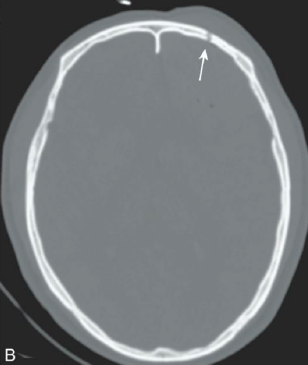

Q

TCE

¿Qué tipo de fractura es esta?

A

Fractura de base de cráneo